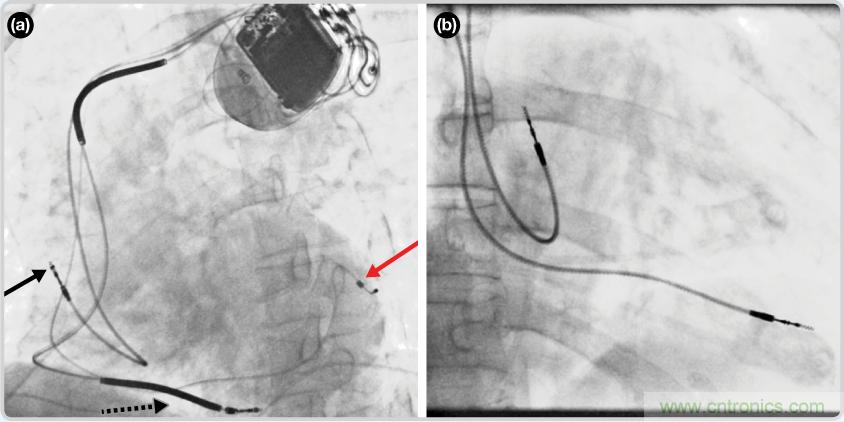

CRT器件在圖4(a)中的透視圖像中可以看見。醫(yī)師就是利用這種影像來放置導(dǎo)聯(lián)線的。對于非專業(yè)人士來說,這種影像是很難解讀的。可以看到心臟淡淡的輪廓——這是搏動中的心臟的靜態(tài)視圖。起搏器位于右心房上,心臟頂點(diǎn)指向右下方。在這個典型的導(dǎo)聯(lián)線放置實(shí)例中,黑色箭頭指向右心房導(dǎo)聯(lián)線。虛線黑色箭頭指向右心室導(dǎo)聯(lián)線。紅色箭頭標(biāo)示的導(dǎo)聯(lián)線只能看到一部分,這是左心室導(dǎo)聯(lián)線(紅箭頭指向電極尖端)。圖4(b)展示的是雙腔起搏器的典型導(dǎo)聯(lián)線放置透視圖像。右心房導(dǎo)聯(lián)線指向上方,置于右心房中。右心室導(dǎo)聯(lián)線則位于右心室頂部。

圖4. 起搏器導(dǎo)聯(lián)線放置的透視圖像3 (a). 單腔起搏器;(b).雙腔起搏器